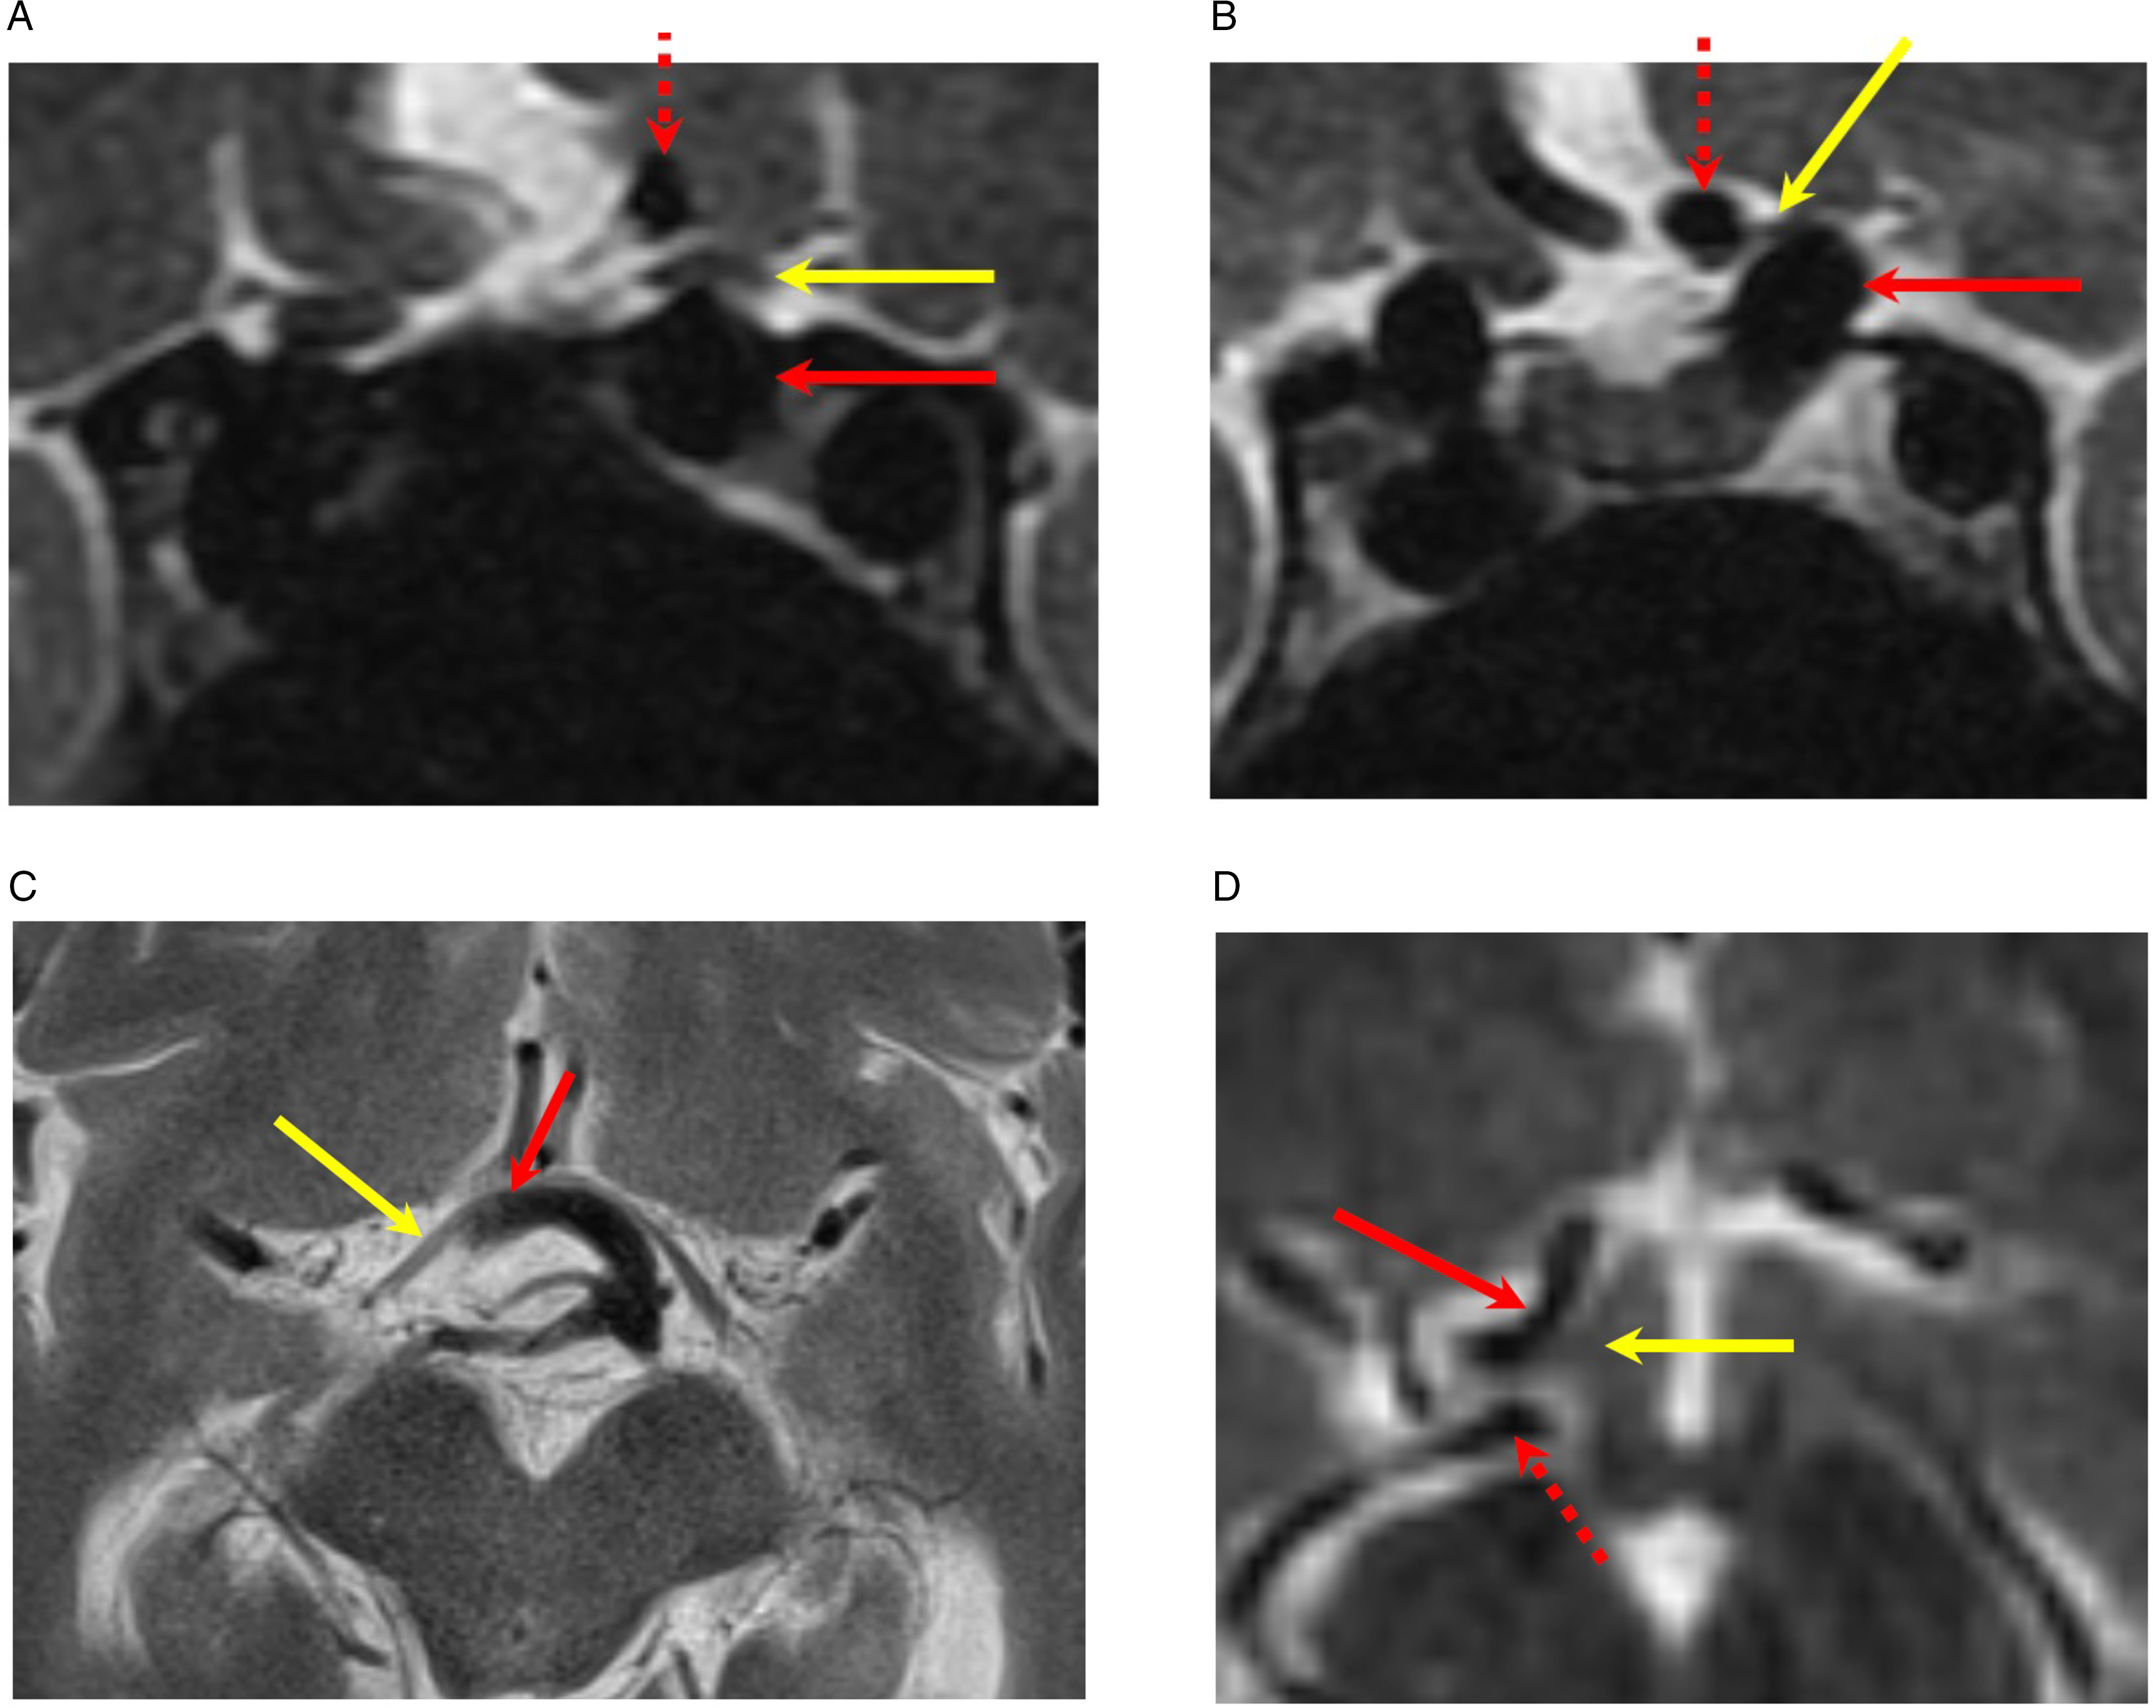

96.5% (28/29) of patients remained stable from the visual perspective during follow-up visits. Figure 1 details HVFs for patients 8, 13, and 24. Figure 2 includes details on T2-weighted MRI images for these patients. Two among the five patients with optic tract compression showed matching homonymous visual field defects (cases 9 and 24). Case 24 presented with significant compression on optic tract and optic chiasm by dolichoectatic basilar artery and showed progression of homonymous quadrantanopia to incongruous homonymous hemianopia. All other patients have remained stable without worsening of vision or visual fields.

Figure 2: MR images. (A and B) Coronal T2-weighted images demonstrate compression of pre-chiasmatic left optic nerve (yellow arrow) by distal cavernous and paraclinoid left internal carotid artery (solid red arrow). The dashed red arrow is the left anterior cerebral artery (patient 13). (C) Axial T2-weighted image demonstrates compression of the right optic tract (yellow arrow) by the dolichoectatic basilar artery (red arrow) (patient 24). (D) Axial T2-weighted image demonstrates compression of the right optic tract (yellow arrow) by the right anterior cerebral artery (solid red arrow). The dashed red arrow is the right posterior cerebral artery. (Patient 8).